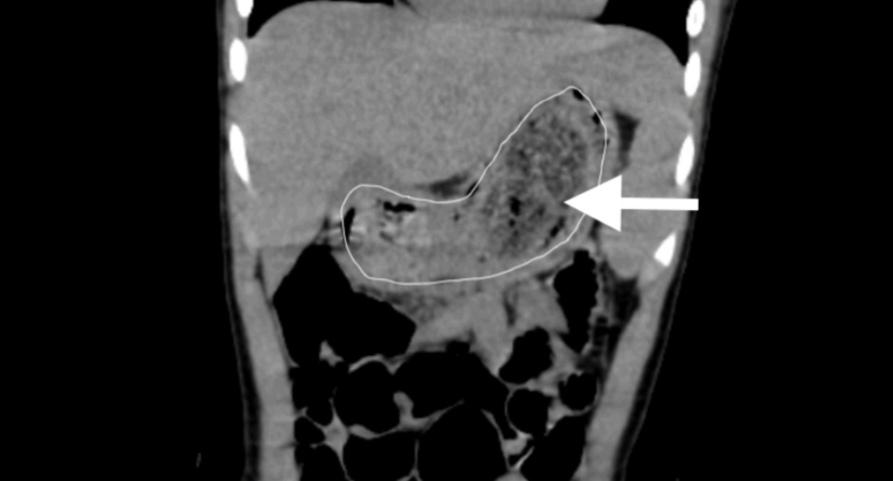

CT检查呈现明明胃内有巨大的毛发石

2个月前,明明出现了剑突下阵发性腹痛,在胃镜下发现,明明的胃内有一个巨大的毛发石。尽管接受了3 次胃镜检查,但当地医院团队仍无法将明明胃内的毛发石完整取出。明明的家长慕名来到中山大学孙逸仙纪念医院,在接受腹部CT检查后,进一步明确了胃内巨大毛发石情况,该院小儿外科主任邓小耿教授团队当即为明明的病情开展了讨论,决定为其实施单孔腹腔镜下胃切开取巨大毛发石术,解决这一持续折磨明明的问题。